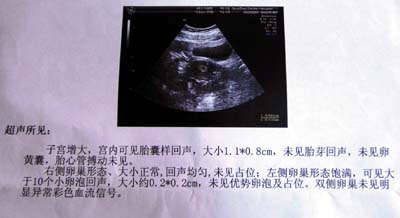

大龄产妇被误诊为宫外孕吃药引产组图

图片尺寸400x218